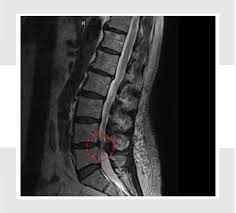

- MRI: 신경압박 정도, 협착 위치·범위 정확하게 파악

🩻 진단 방법